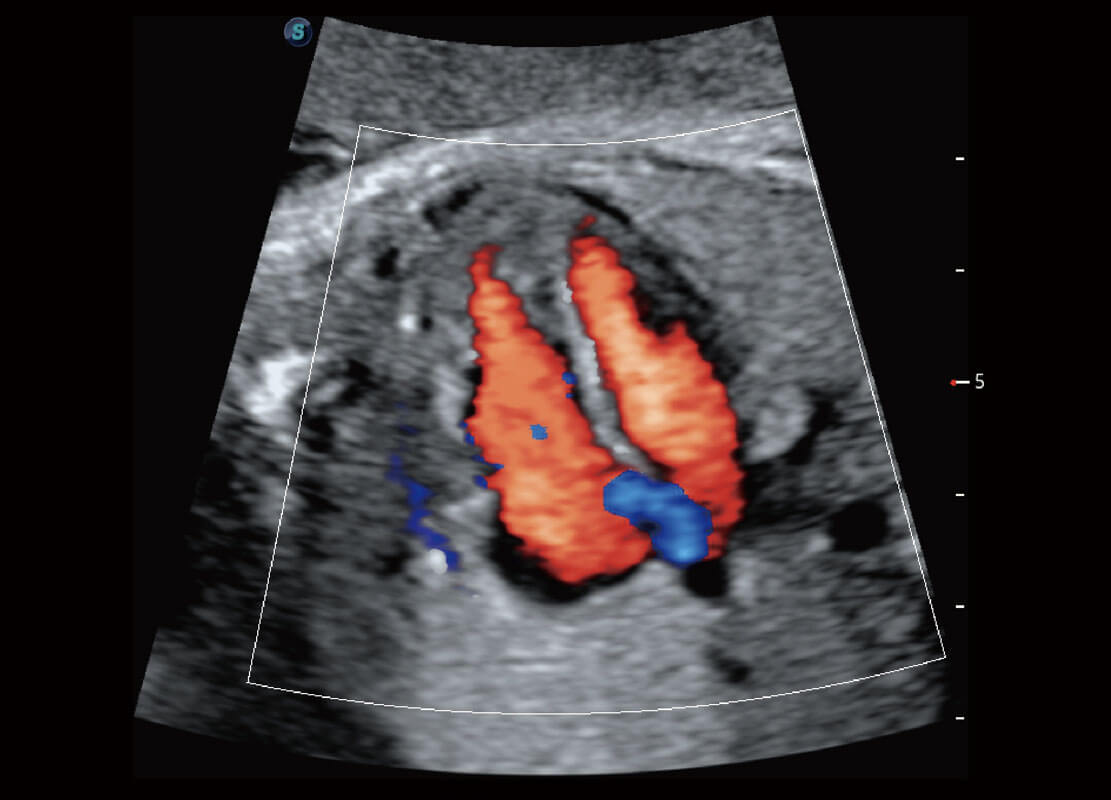

胎儿体循环

P60搭载一系列胎儿心脏成像技术,实现精细的胎儿心脏评估。

四腔心血流

胎心容积成像